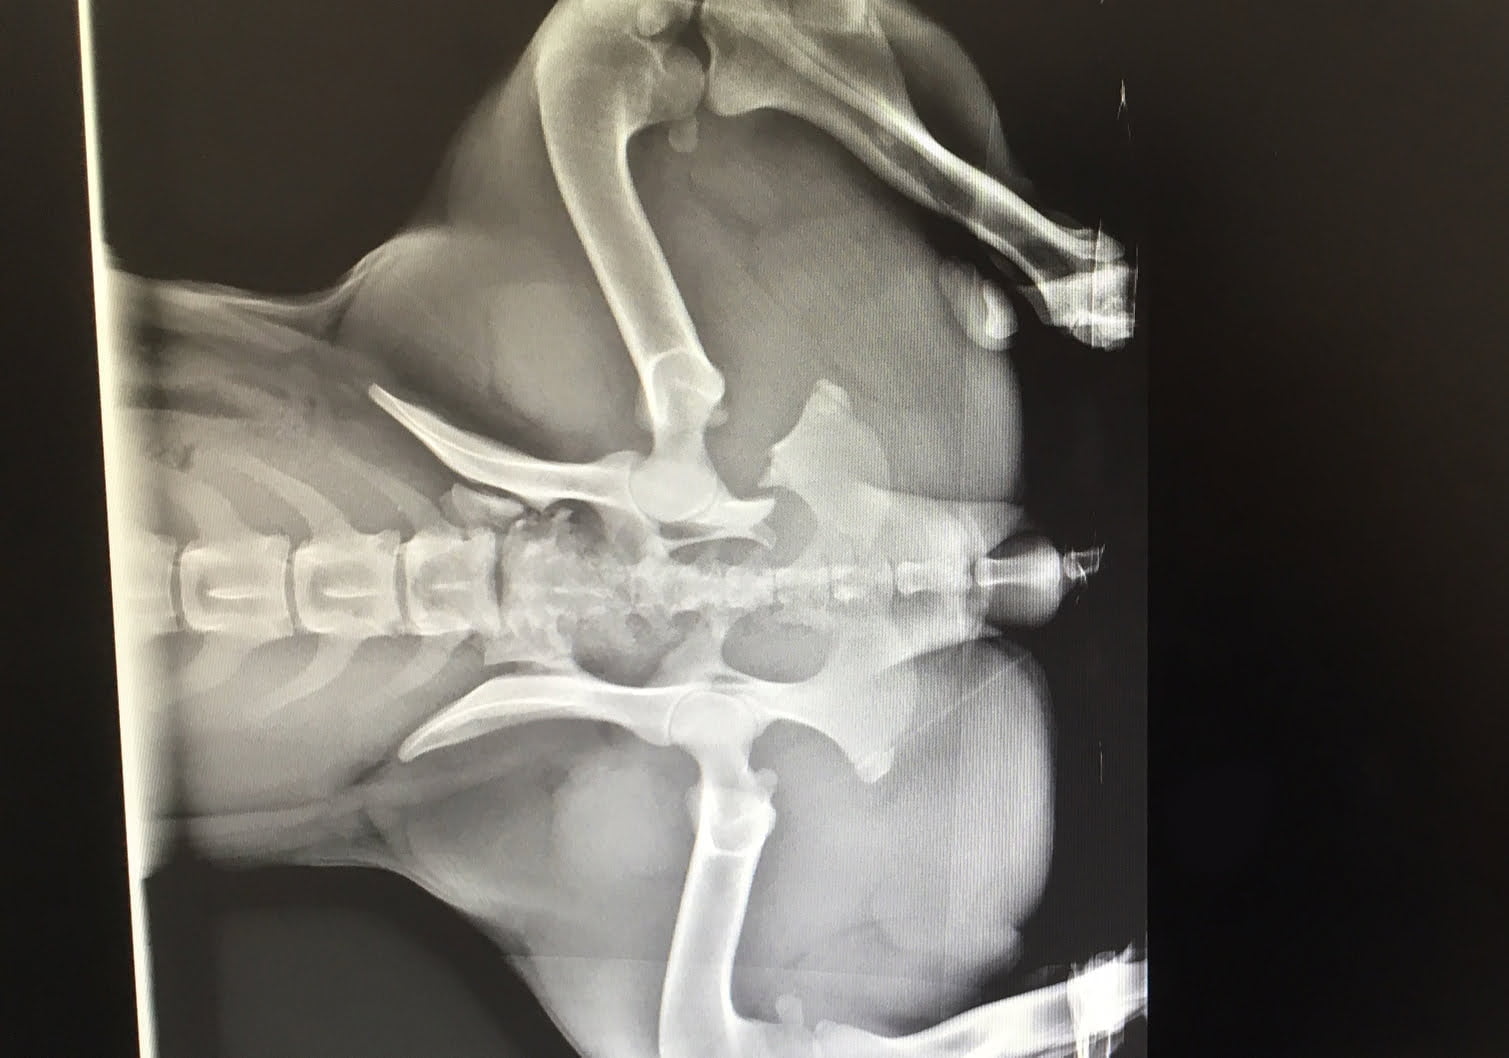

Après avoir été heurtée par une voiture, Mia, une chienne âgée d’environ 3 ans a été amenée à la SPCA de Montréal par un bon samaritain qui l’avait trouvée blessée. À son arrivée, elle était visiblement souffrante et peinait à marcher. Grâce aux nouveaux appareils de radiographie de la SPCA, notre équipe vétérinaire a pu évaluer tout de suite la gravité de ses blessures.

Les radiographies ont rapidement révélé de multiples fractures du bassin. Heureusement, en fonction des signes cliniques, une intervention chirurgicale n’était pas nécessaire et le pronostic était bon. Mia devait dès lors rester au repos forcé avec analgésie pour une période de huit semaines afin de permettre à ses os fracturés de se ressouder. Toutefois, il était important de faire des suivis radiographiques pour s’assurer que les choses n’empiraient pas avec le temps.

Lors de leur dernière visite, Mia et sa famille d’accueil ont reçu d’excellentes nouvelles : le bassin de la chienne était presque rétabli. Afin de guérir complètement, Mia doit maintenant faire des exercices de physiothérapie quotidiennement. Elle sera bientôt à la recherche d’une famille qui pourra continuer de veiller sur elle à vie.